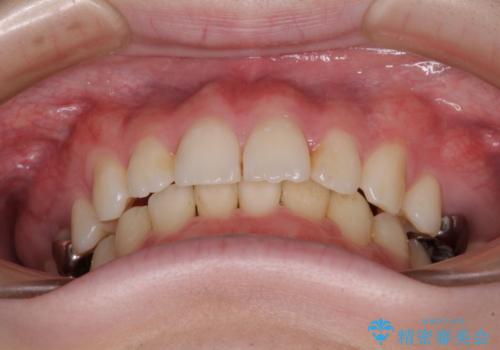

萌出が不十分な歯はインビザラインで引き出すことができないため、ワイヤー装置などの併用が必須となります。

今回は部分的にワイヤー矯正を用いましたが、右下の乳歯は全く動かなかったため、抜歯をした上でインプラントを埋入し、オールセラミッククラウンにて補綴治療を行いました。